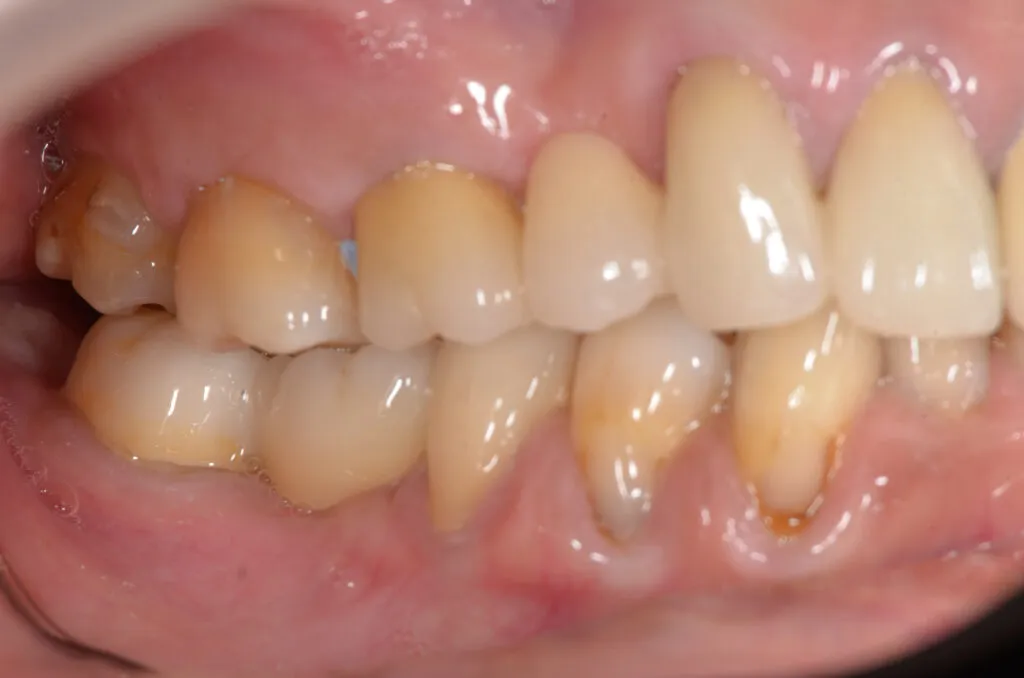

部分矯正(MTM…マイナー・トゥース・ムーブメント)とは、動かす歯を1本~数本に限定して矯正治療を行う方法です。

部分矯正は、動かす歯を1本~数本に限定して矯正治療を行うので、短い期間で症状を改善できます。被せものを併用した場合はさらに短期間で治療を終えることも可能です。

隙間があいている前歯を移動させる場合や、傾いている歯をまっすぐに修正する場合に有効な治療法です。またむし歯が骨の中まで進行した場合、通常は歯を抜くことになりますが、歯を引っ張りあげることで、保存できる場合もあります。